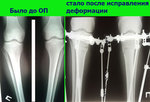

Исходник отличный, внутренний контур голеней чётко выражен.

Дата операции 09.02.2016г.

Рентген в 20 дней после операции.

Ортопедическая ось идеальная, искусство хирурга на 5+

Зафиксировать аппараты и домой!